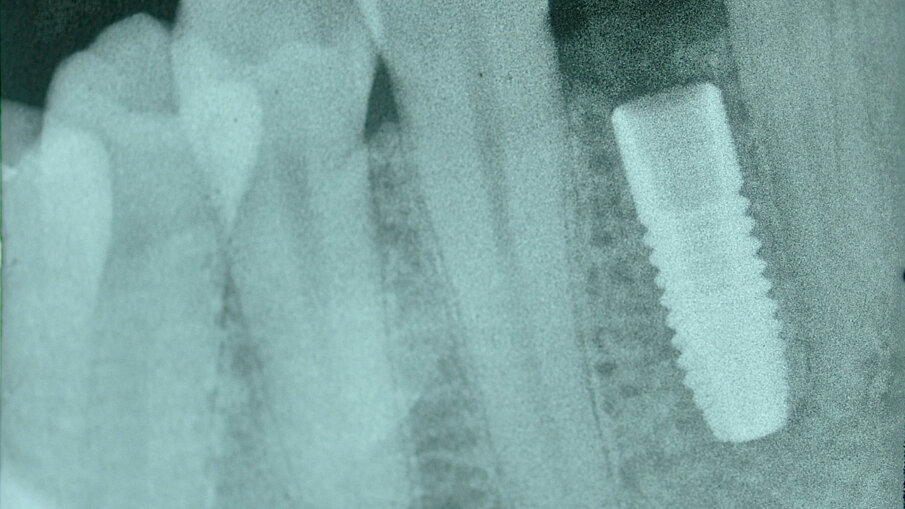

40letý pacient s chybějícím pravým postranním řezákem v dolní čelisti a štěpem transplantovaným do oblasti tohoto chybějícího zubu požádal o rekonstrukci za použití dentálního implantátu. U tohoto typu náhrady je problémem omezený dostupný prostor a blízkost sousedních zubů. Při klinickém vyšetření byl posouzen dostupný prostor (obr. 1) a na periapikálním RTG snímku pořízeném před ošetřením byla vyhodnocena oblast pro zavedení implantátu (obr. 2). Plán ošetření zahrnoval konvenční zavedení implantátu za použití implantátu OsseoSpeed EV (Dentsply Sirona) a bezprostředně po zavedení implantátu byla nasazena provizorní náhrada na abutmentu Temporary Abutment EV (Dentsply Sirona). Pro definitivní náhradu bylo naplánováno použít za účelem obnovy přirozeného vzhledu a funkce chybějícího zubu korunku na abutmentu Atlantis Crown Abutment (Dentsply Sirona).

Zavedení implantátu